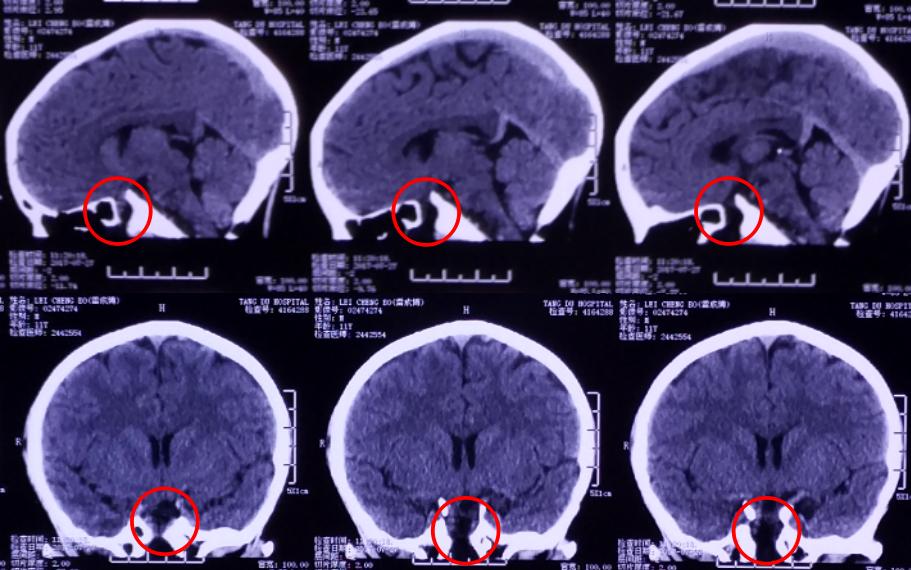

4、患者近期做头颅磁共振提示:鞍区占位性病变;

影像资料